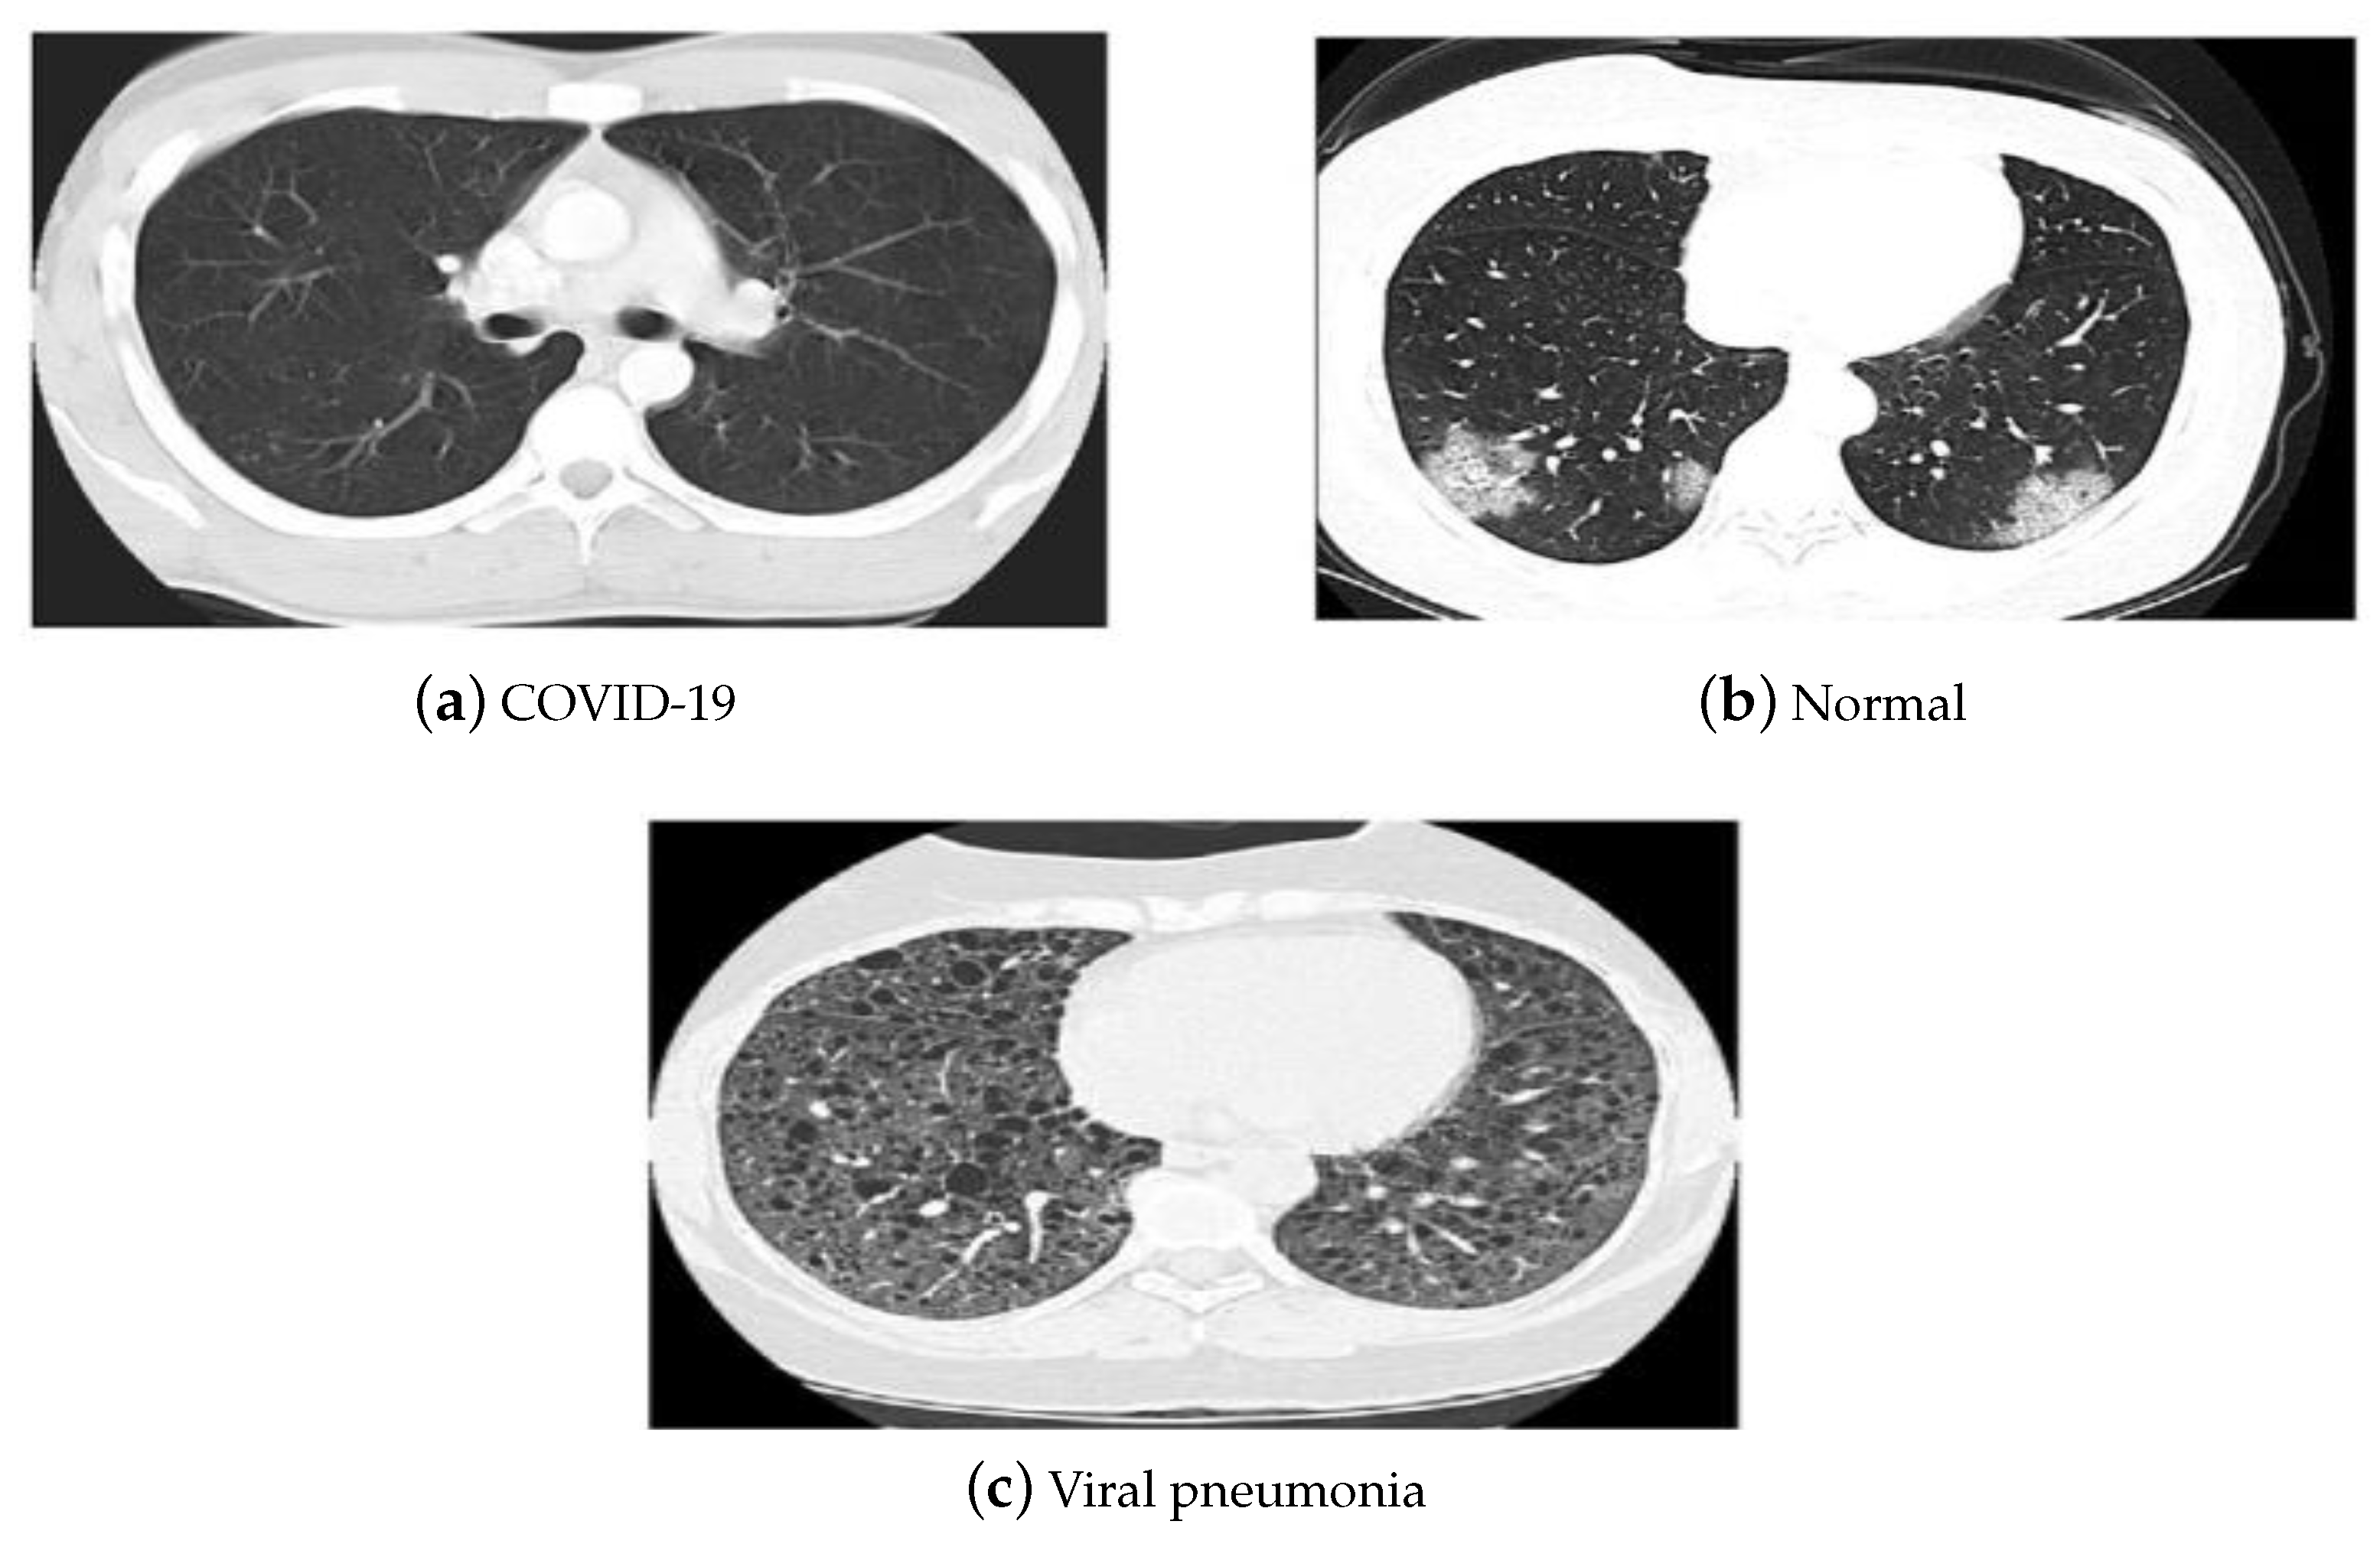

The China National Center for Bio-information CT chest imaging data set [53] was also employed in our investigations. The images of the data set are classified as coronavirus pneumonia, common pneumonia, and normal. The data set includes 617,775 CT slices from 6752 CT scans for 4154 patients. It consists of CT images for 999 COVID-19 patients, and 1687 normal and 1468 common pneumonia patients. Figure 5 depicts the CT samples of the utilized data sets leveraged in our investigations.

Figure 5.

(a–c) CT data set samples [53].